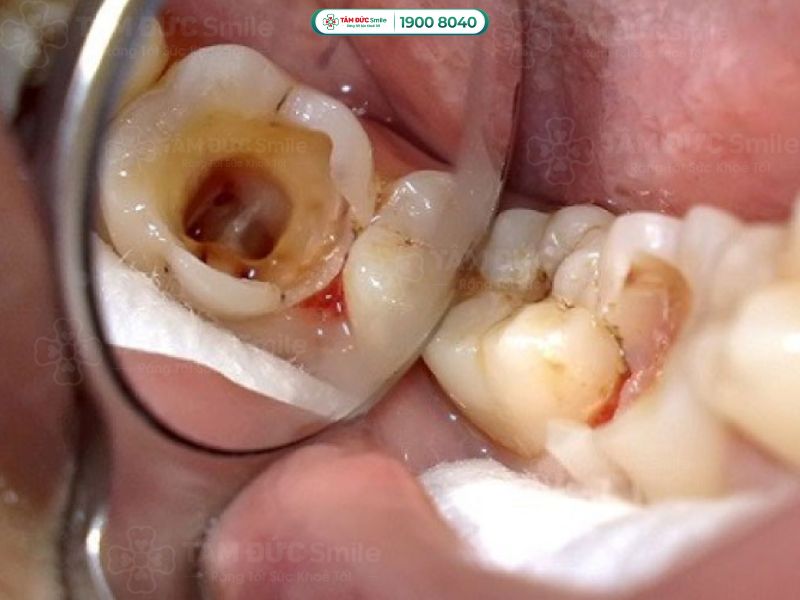

Răng sâu cấp độ 3, 4 là khi vi khuẩn đã xâm nhập sâu vào cấu trúc răng và ảnh hưởng đến tủy răng. Ở cấp độ 3, sâu răng đã lan rộng sâu bên trong ngà răng, gây ra cảm giác đau nhức và ê buốt thường xuyên. Khi răng sâu tiến triển đến cấp độ 4, tủy răng bị viêm nhiễm nặng, dẫn đến những cơn đau dữ dội và kéo dài. Lúc này, tủy răng sẽ bị chết, tạo điều kiện cho vi khuẩn lan xuống vùng chân răng, gây nhiễm trùng lan rộng và áp xe chân răng.

Hầu hết các trường hợp răng sâu cấp độ 3 và 4 đều cần phải lấy tủy. Lấy tủy răng giúp loại bỏ phần tủy bị viêm nhiễm hoặc hoại tử, ngăn chặn nhiễm trùng lan rộng và bảo vệ sức khỏe răng miệng. Sau khi lấy tủy, bác sĩ sẽ tư vấn bạn bọc răng sứ để bảo vệ và phục hồi chức năng ăn nhai của răng.